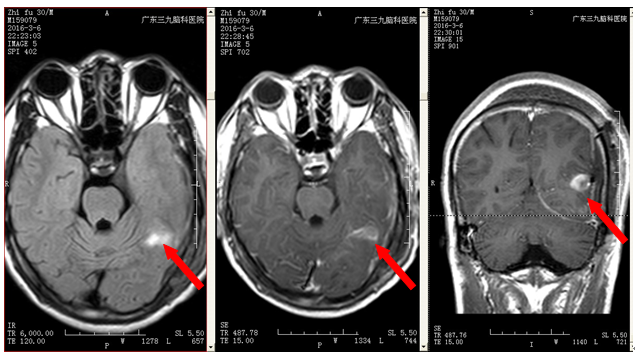

植先生,因3个月前无明显诱因出现四肢抽搐,伴意识障碍,伴抽搐后头痛,遂就诊当地医院,颅MR提示:左侧枕颞叶交界处底部占位性病变,为求进一步治疗来我院就诊,入院后完善相关检查,行左侧枕颞叶交界处占位性病变切除术+ICP探头置入术,术程顺利,病理提示:左侧枕颞叶交界处胚胎发育不良性神经上皮肿瘤(DNT,WHO 1级),术后恢复良好。

术后检查

该病变属于胚胎发育不良性神经上皮瘤(DNT),主要见于青少年,男性患者稍多于女性。DNT主要表现为难治性部分性癫痫发作,少数为复杂部分发作。对于影像学,CT通常表现为皮层内边界清楚的低密度病灶,注药无强化,瘤周无水肿,占位效应不明显。MRI表现:T1表现为低信号,T2表现为高信号的边界清楚的病灶,病变周围无水肿,无明显占位效果,注药后有20%-30%的病变出现轻度局灶性强化。1.对曾经有癫痫大发作、头痛患者要引起警惕,及时去医院检查。2.有局部癫痫发作者,应高度警惕发生本病的可能。DNT只能行手术治疗,预后良好,手术切除后不需要行放疗及化疗。术后病变复发率及低,少数病人可能出现复发及恶变。